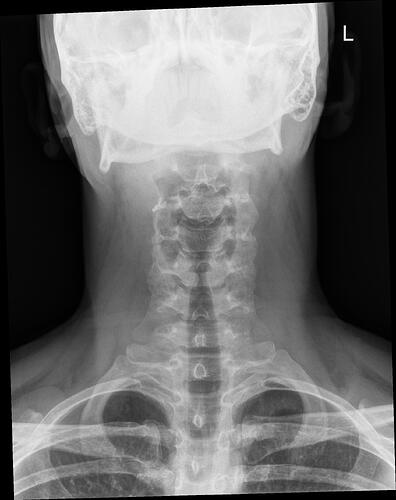

A few days ago, I started having swallowing difficulties. When I reached to the back of my mouth with my finger, I was shocked to feel a bony structure instead of the normal soft tissue. Since it was late and I had little access to my GP, I used ChatGPT, which suggested it might be Eagle syndrome. I then did some research and found your group.

What worries me is that my oxygen supply to the brain may have been limited for so long that it caused structural neural damage. I will ask my GP and push hard for a CT scan of my neck. But I want to ask you: have any of you had similar issues, and after the operation, did your symptoms—even if severe initially—resolve completely, especially cognitive ones?